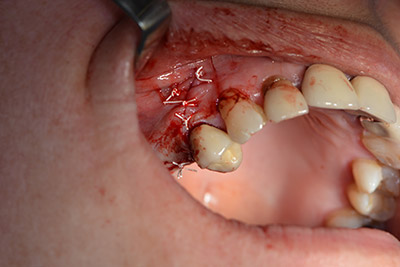

Una membrana reabsorbible formó la barrera en sentido bucal y cubrió el aumento. Por último se procedió a la sutura de modo que no penetrara saliva (figuras 15 a 19).